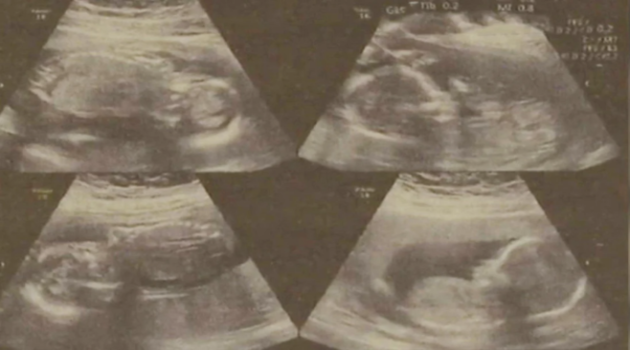

Reportan insólito caso con embarazada china de cuatrillizos

Una embarazada de cuatrillizos en la ciudad china de Jining (provincia de Shandong), dio a luz de forma prematura a dos de sus bebés en días distintos y los restantes continúan gestándose en su útero.

Según informó el diario South China Morning Post, el primero de ellos nació el pasado 22 de marzo a las 25 semanas y 6 días de embarazo; y cuatro días después tuvo el segundo parto.